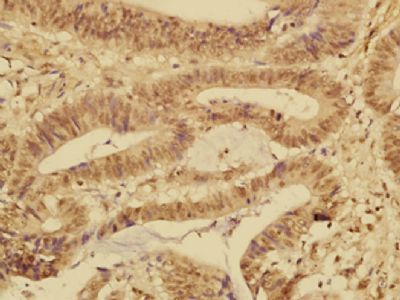

IHC (Immunohistochemistry)

(Paraformaldehyde-fixed, paraffin embedded (Human colon carcinoma); Antigen retrieval by boiling in sodium citrate buffer (pH6.0) for 15min; Block endogenous peroxidase by 3% hydrogen peroxide for 20 minutes; Blocking buffer (normal goat serum) at 37 degree C for 30min; Antibody incubation with (FABP12) Polyclonal Antibody, Unconjugated (bs-13064R) at 1:500 overnight at 4 degree C, followed by a conjugated secondary (sp-0023) for 20 minutes and DAB staining.)